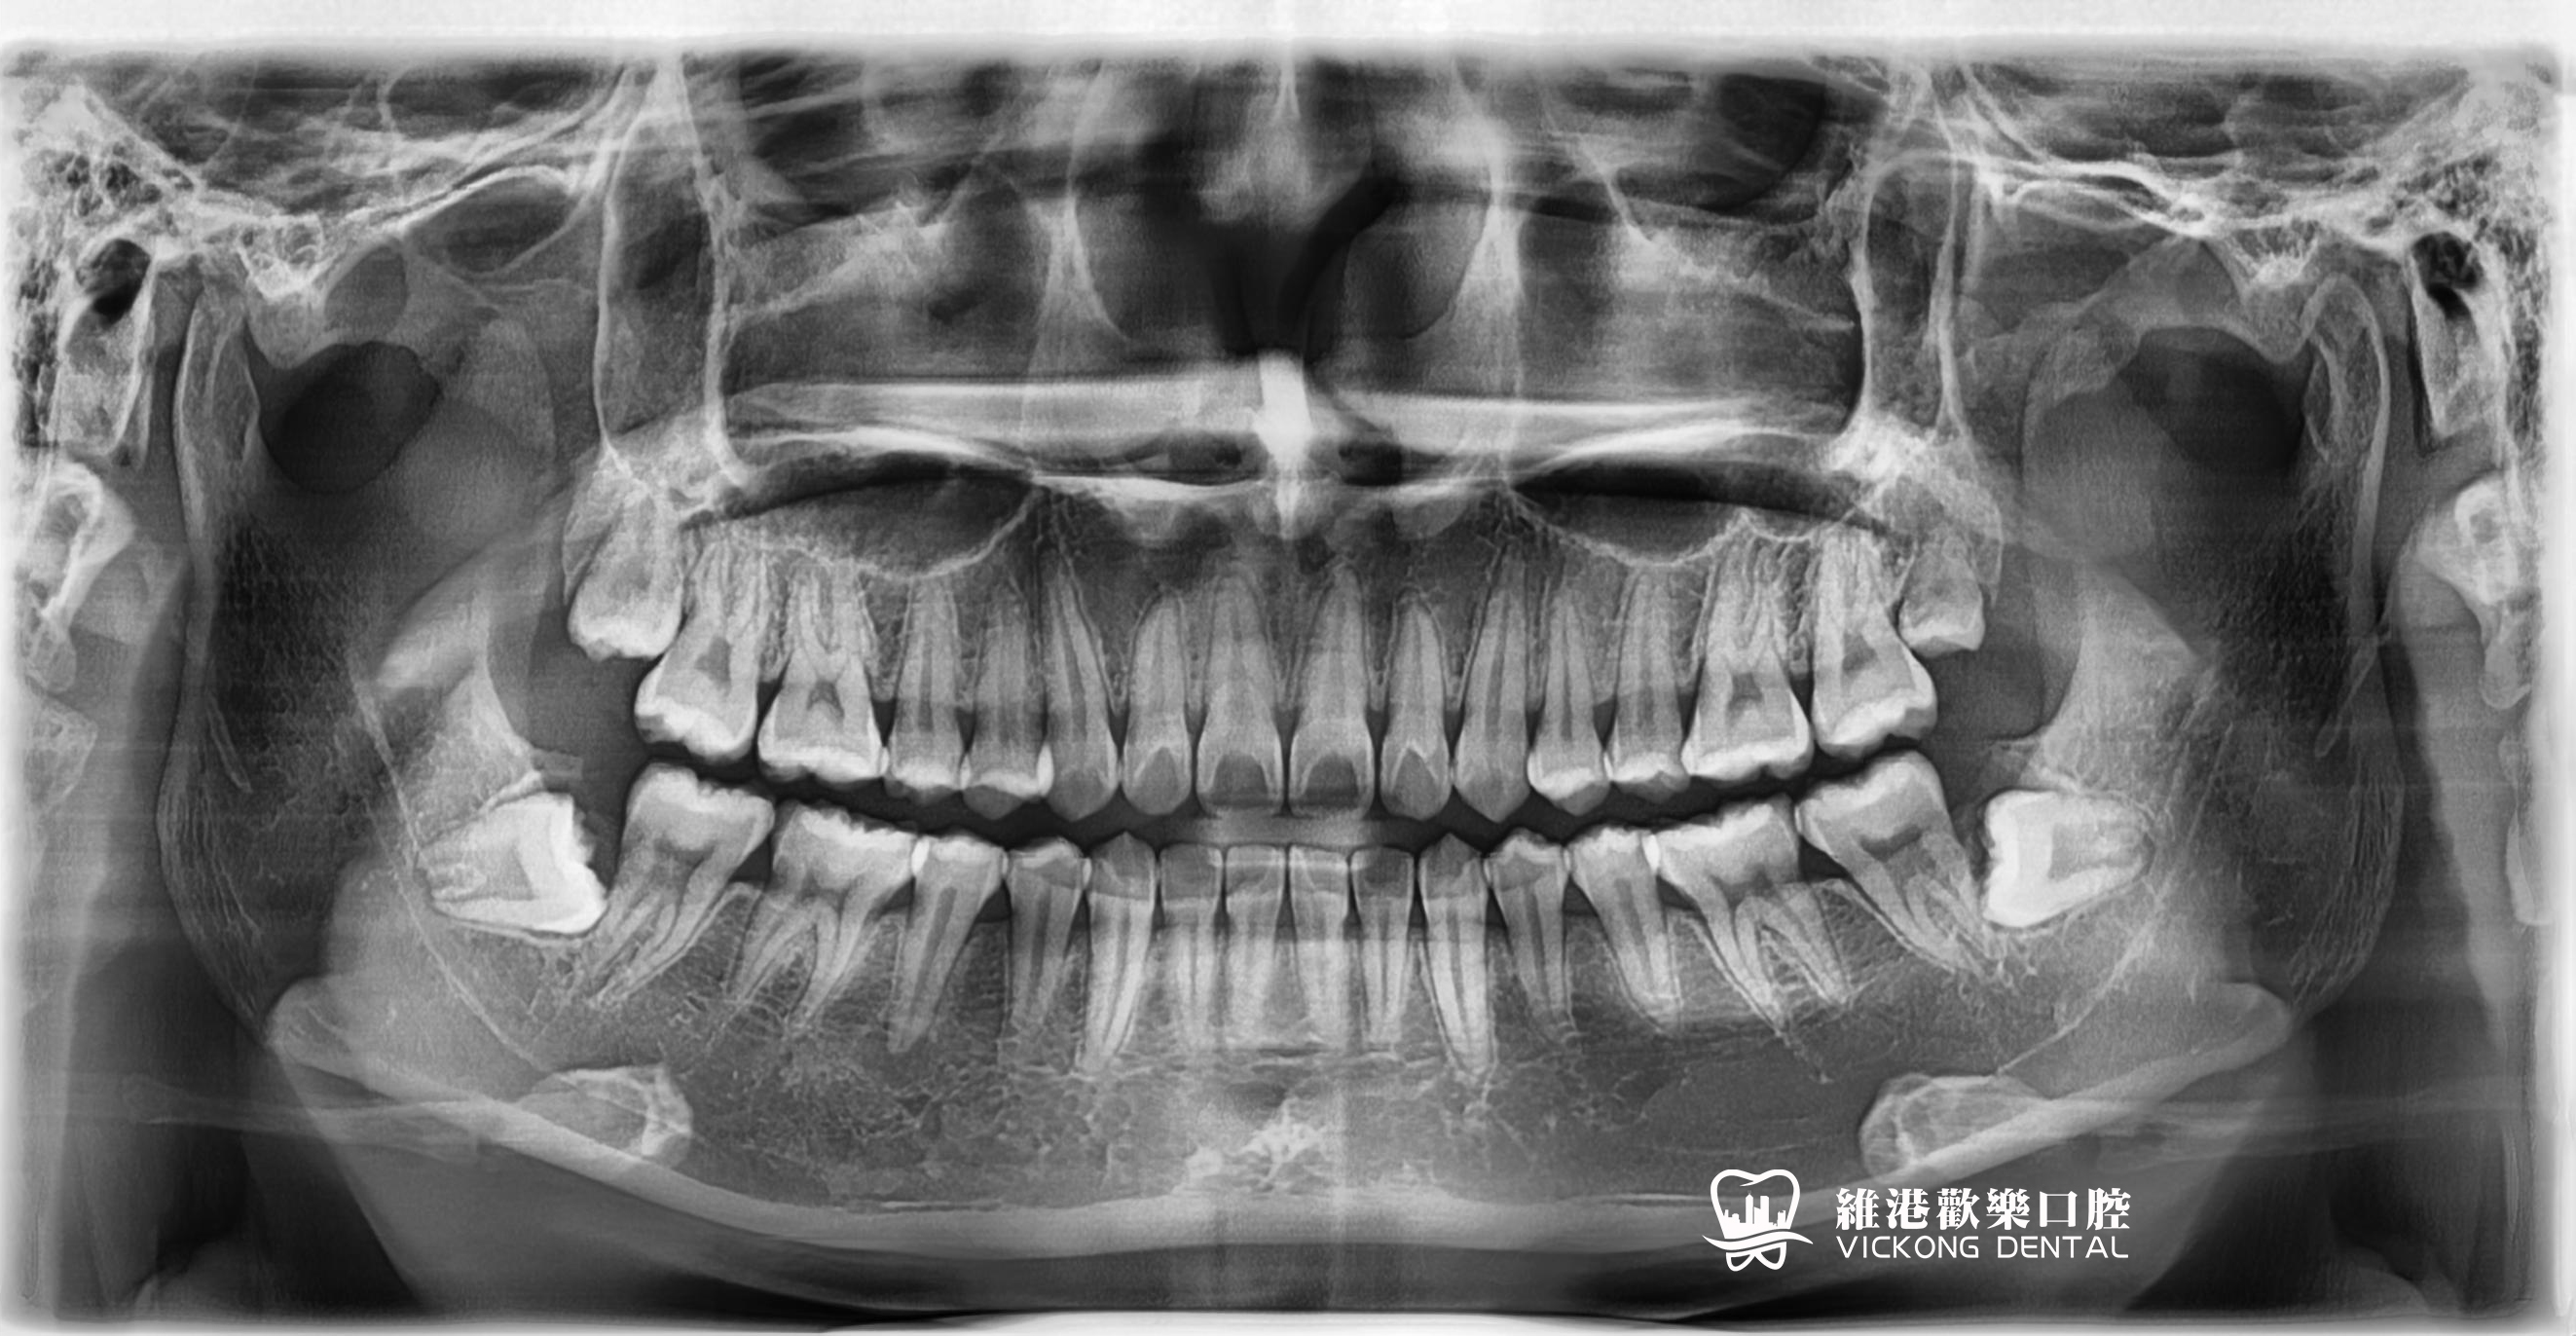

深圳維港歡樂口腔-陳培章醫生微創種植牙案例

深圳維港歡樂口腔-陳培章醫生拔除阻生智慧齒